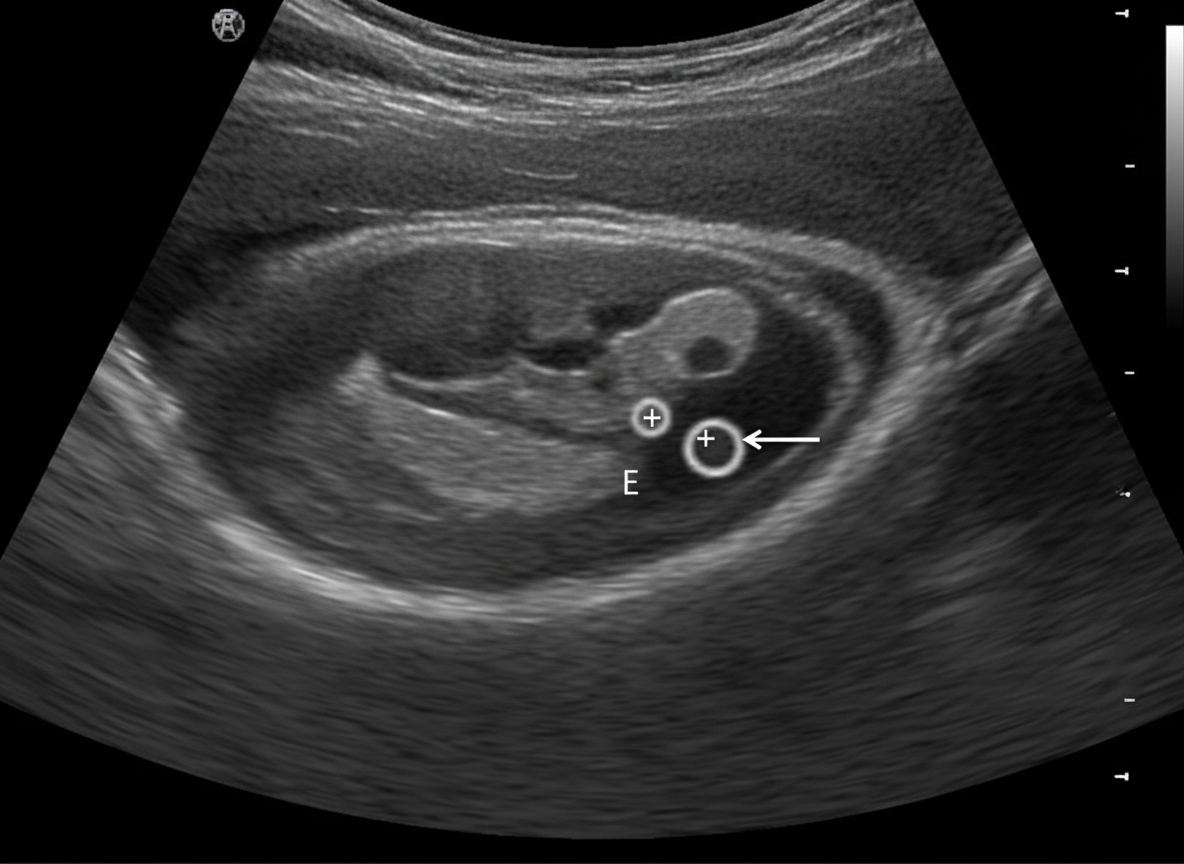

A sonogram demonstrates a Crown-Rump Length (CRL) of an 8-week fetus. The arrow in the image points to which of the following structures?

Explanation: ***Yolk sac*** - The **yolk sac** appears as a round, **echogenic ring** measuring approximately **3-5 mm** in diameter, located adjacent to the embryo within the gestational sac at 8 weeks gestation. - It serves as an important **sonographic landmark** for confirming **intrauterine pregnancy** and provides early nutrition to the developing embryo before placental circulation is established. *Blighted ovum* - A **blighted ovum** (anembryonic pregnancy) refers to an **empty gestational sac** without a visible embryo or yolk sac. - Since this case shows a **measurable CRL** indicating a viable 8-week fetus, a blighted ovum is not possible. *Pseudo-gestational sac* - A **pseudo-gestational sac** is associated with **ectopic pregnancy** and appears as fluid collection in the uterine cavity without a true **decidual reaction**. - The presence of a **measurable embryo with CRL** confirms an **intrauterine pregnancy**, ruling out this possibility. *Gestational sac* - The **gestational sac** is the larger, **anechoic (dark)** fluid-filled structure that surrounds the entire pregnancy, not the small echogenic ring being pointed to. - At 8 weeks, the gestational sac measures approximately **25-30 mm**, much larger than the structure indicated by the arrow.